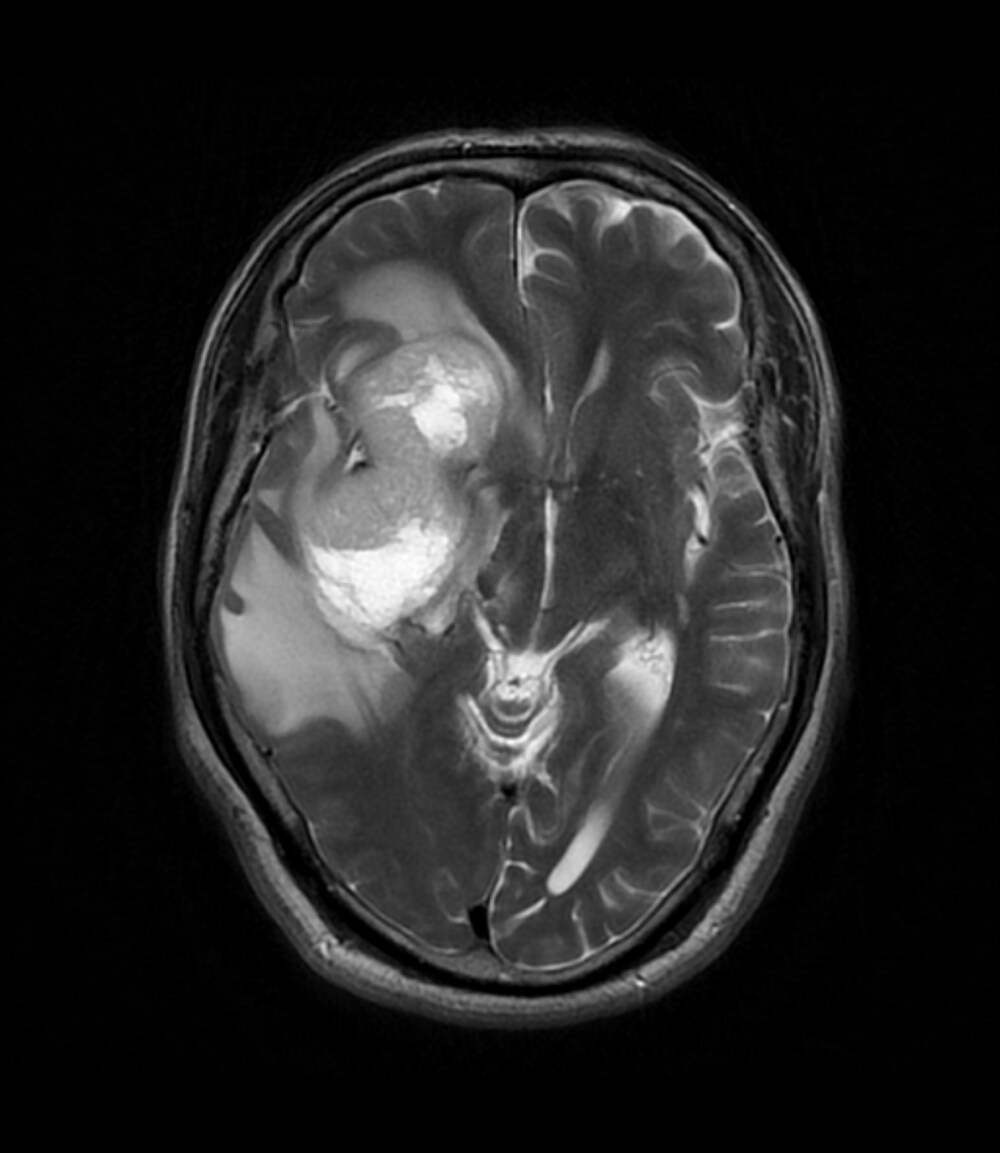

2週間前からの頭痛にて前医を受診し、CTで頭蓋内腫瘤や脳浮腫を認めたため、当院へ救急搬送された。当院で施行された造影MRIでは右側頭葉~前頭葉に約7.5×4cmの辺縁不整な腫瘤を認め、膠芽腫が疑われた。その後手術が施行され膠芽腫の診断に至り、手術後は化学放射線治療が施行された。

当該疾患の診断における造影MRIの役割

受診当日に施行されたCT/MRIにて偶発的に腫瘤が発見された。非造影のCTやT1強調画像、T2強調画像、拡散強調画像などでは腫瘤の存在や輪郭が不明瞭であることも多く、本症例のように造影を行うことで腫瘤の詳細な評価が可能となる。一般的には転移性脳腫瘍や脳膿瘍などが鑑別となり、その他のシーケンスや体幹部の所見、臨床データなどとも併せて診断を行うことが重要である。